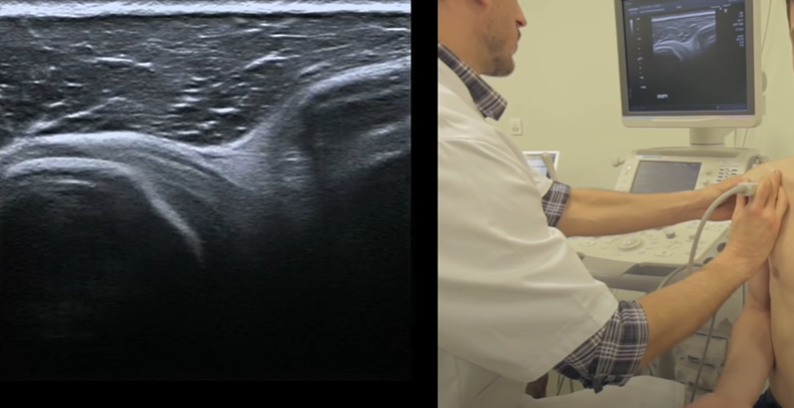

- Manoeuvres dynamiques en axial (ouvrir et fermer l’épaule, regarder le comportement du tendon sous le coracoide

Manoeuvres dynamiques rotation